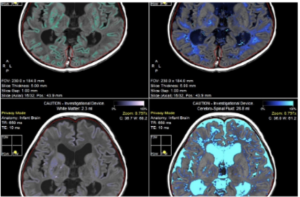

That is exactly what MYR-101 does. By precisely targeting oligodendrocytes, which are the cells responsible for myelin production, Myrtelle’s therapy addresses the source of Canavan disease rather than managing its symptoms.

The results published in Nature Medicine in September 2025 confirmed that MYR-101 restored myelin and reduced toxic NAA levels in treated children.

These findings represent an important step toward developing a disease-modifying therapy for Canavan disease. And critically, this platform isn’t limited to Canavan disease.